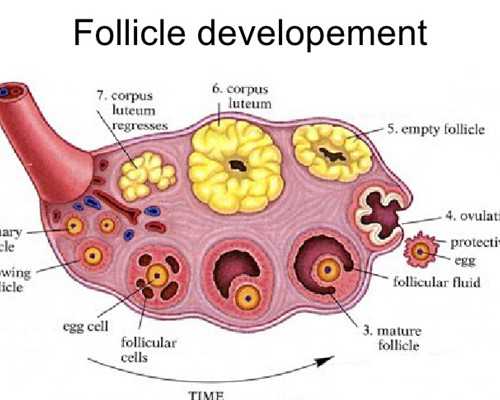

1、卵巢垂體功能檢查:了解女方排卵日期、有無排卵日期和有無排卵功能障礙。可通過基礎體溫測定、宮頸粘液檢查或性激素測定來進行檢查。